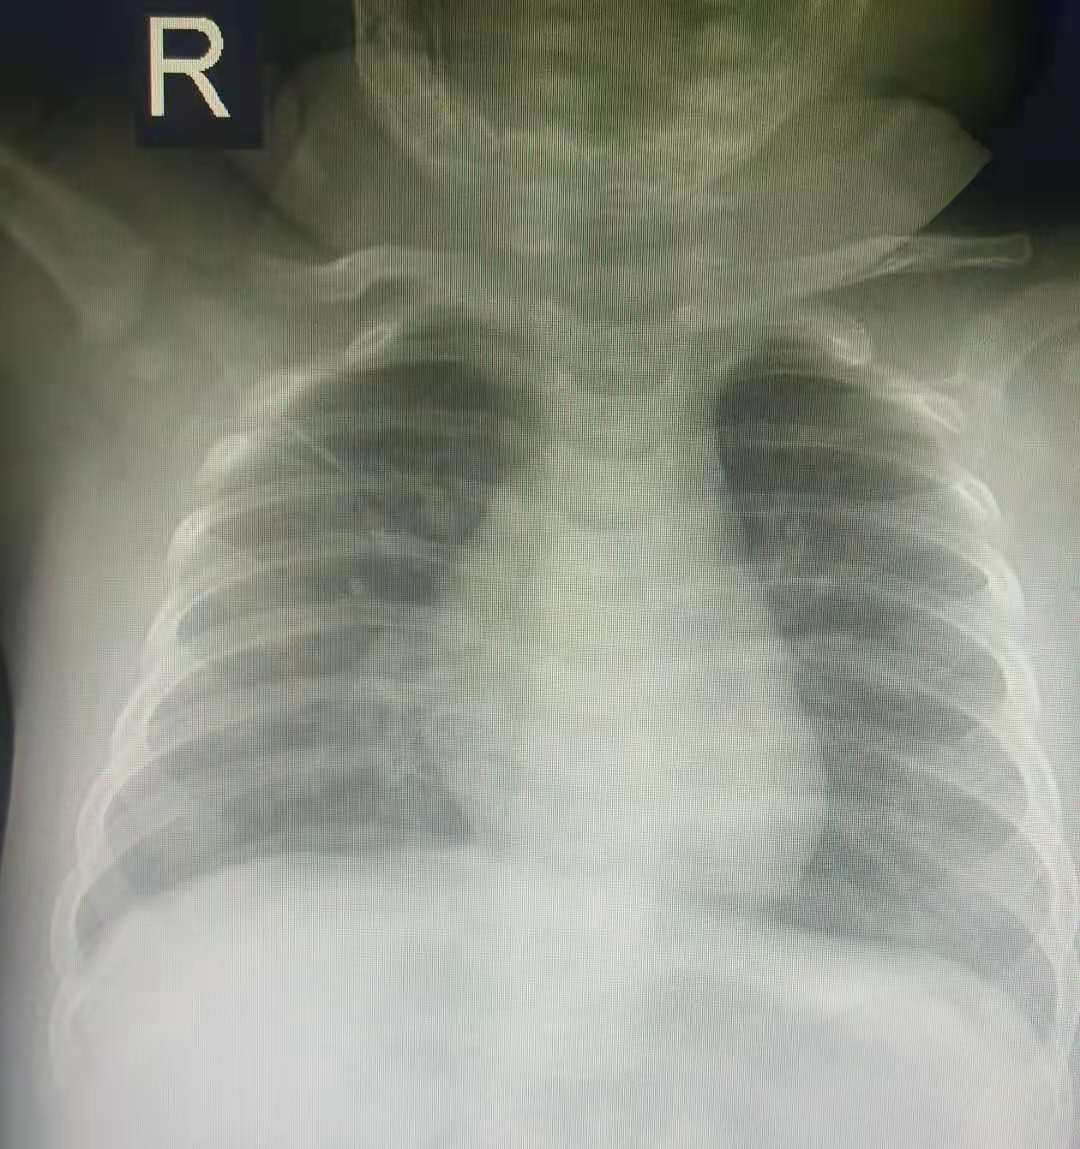

入院后完善各项相关检查,查血常规五分类白细胞数目(WBC),7.81x10^9/L,L;嗜酸性粒细胞百分比(EO%),0.3%,L;血小板数目(PLT),418x10^9/L,H;血小板压积(PCT),0.410%,H 。胸部正位平检查意见:符合支气管肺炎改变。肺炎支原体IgM抗体检测、降钙素原、CRP、心肌酶谱六项、血清铁未见异常;尿常规+尿沉渣:正常。